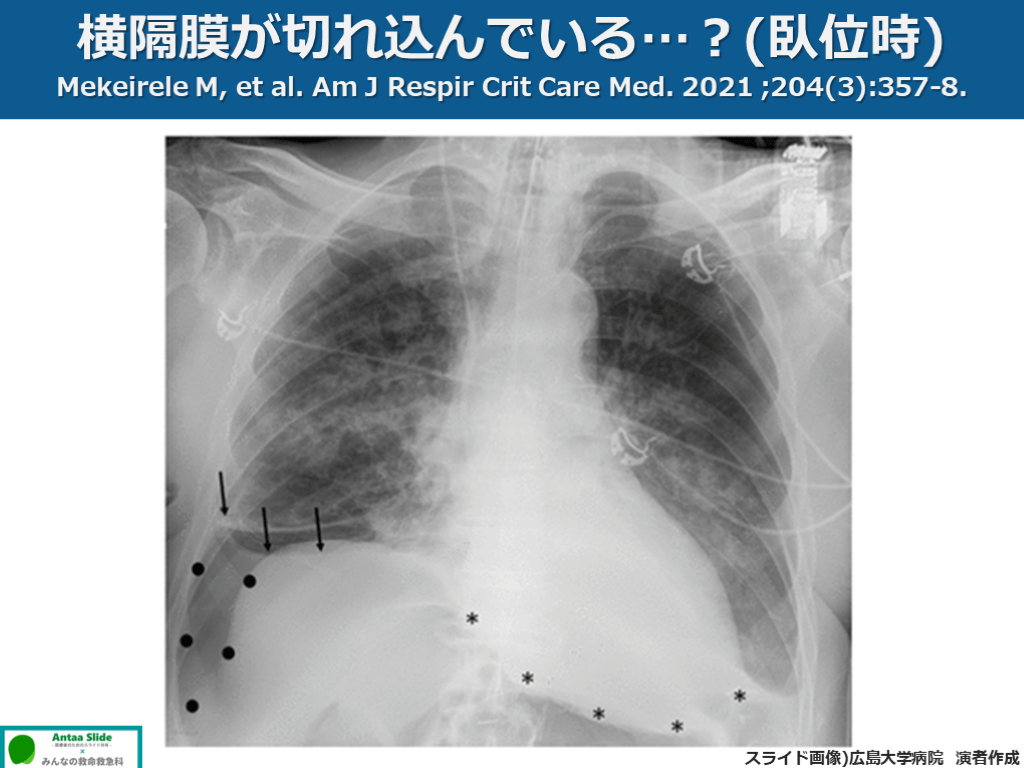

横隔膜が切れ込んでいる…?(臥位時) Mekeirele M, et al. Am J Respir Crit Care Med. 2021 ;204(3):357-8. スライド画像)広島大学病院 演者作成

気胸! Deep sulcus sign 横隔膜が切れ込んでいる…?(臥位時) Mekeirele M, et al. Am J Respir Crit Care Med. 2021 ;204(3):357-8. スライド画像)広島大学病院 演者作成